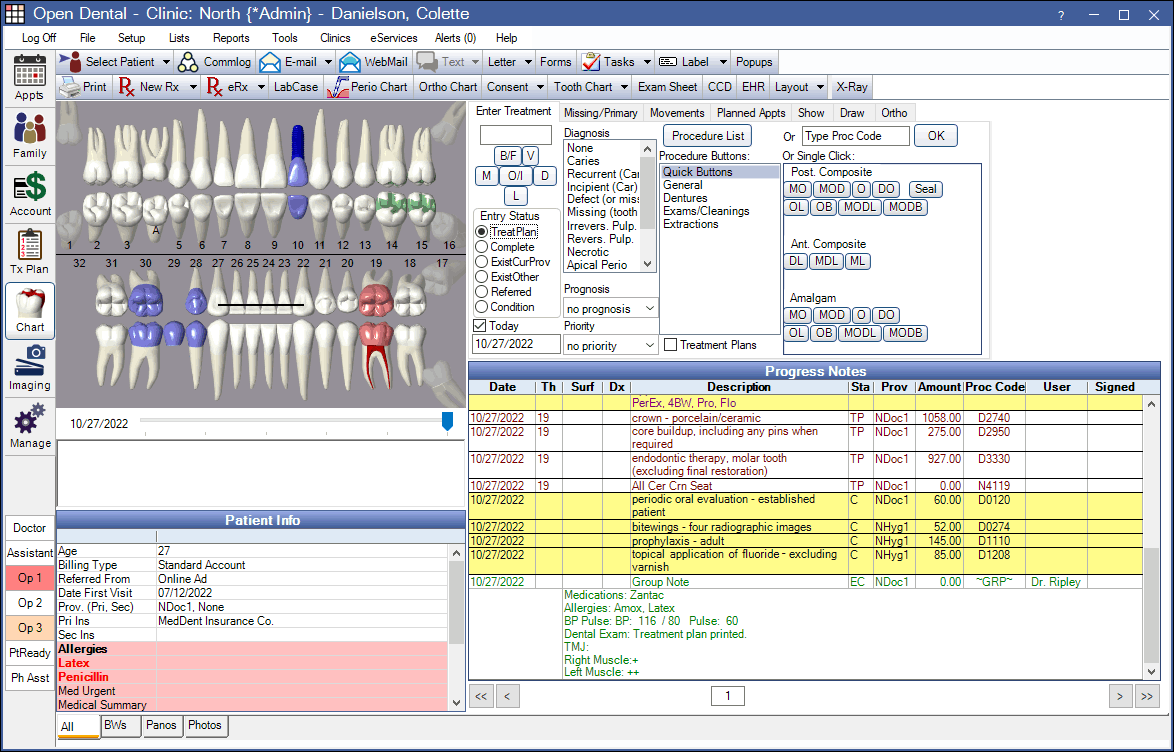

Dental Practice Management Software

OpenDental is a comprehensive dental practice management software designed to streamline various administrative tasks and enhance patient care. Its key features include appointment scheduling, patient records management, billing and invoicing, insurance claim processing, treatment planning, imaging integration (such as X-rays), and reporting functionalities.

It supports customization and integrates seamlessly with third-party applications, allowing practices to adapt the software to their unique needs. It is also highly scalable.

Additionally, it offers robust security features to ensure patient data is protected and complies with HIPAA regulations. OpenDental continuously evolves to meet the dynamic demands of dental professionals.

Scalability

Desktop based customizable dental practice mgmt software

Salient

- Tooth Charting

- Billing Processsing.

- Appt. Scheduling.